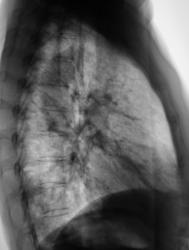

После проведения противовоспалительной терапии проведен "контроль".

Ваше мнение уважаемые коллеги?

А млжет быть эти крупные очаги - метастазы?